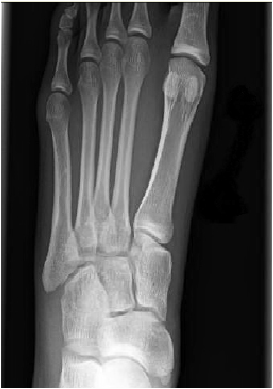

/As emergency medicine physicians, we are expected to put our best foot forward in the thorough evaluation of lower extremity injuries. In this Quick Hit, Dr. Banning walks us through the identification and management of a relatively rare but important podiatric injury.